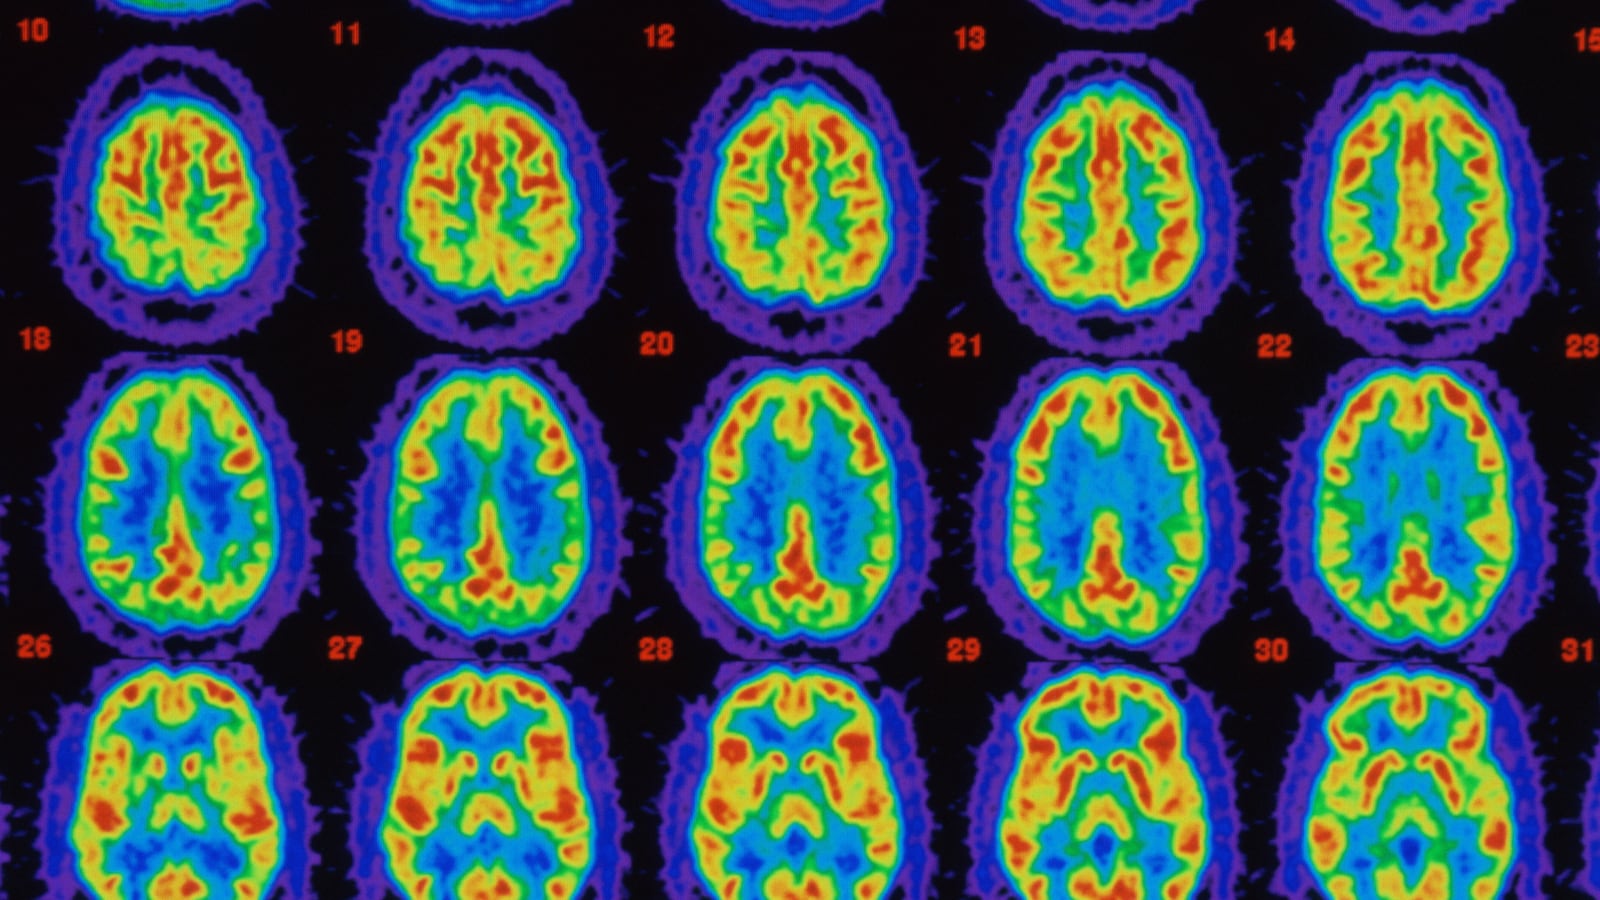

In fact, more than 100 drugs for Alzheimer’s disease have either failed in development or been abandoned. Beta amyloid, which OL-1 is meant to lower, was first implicated in the disease at its identification by Alois Alzheimer in 1906. Many researchers believe that the dementia from Alzheimer’s disease is caused by an accumulation of beta amyloid in the brain, forming plaques that choke healthy cells, leading to the loss of neurons and, eventually, problems with thought.